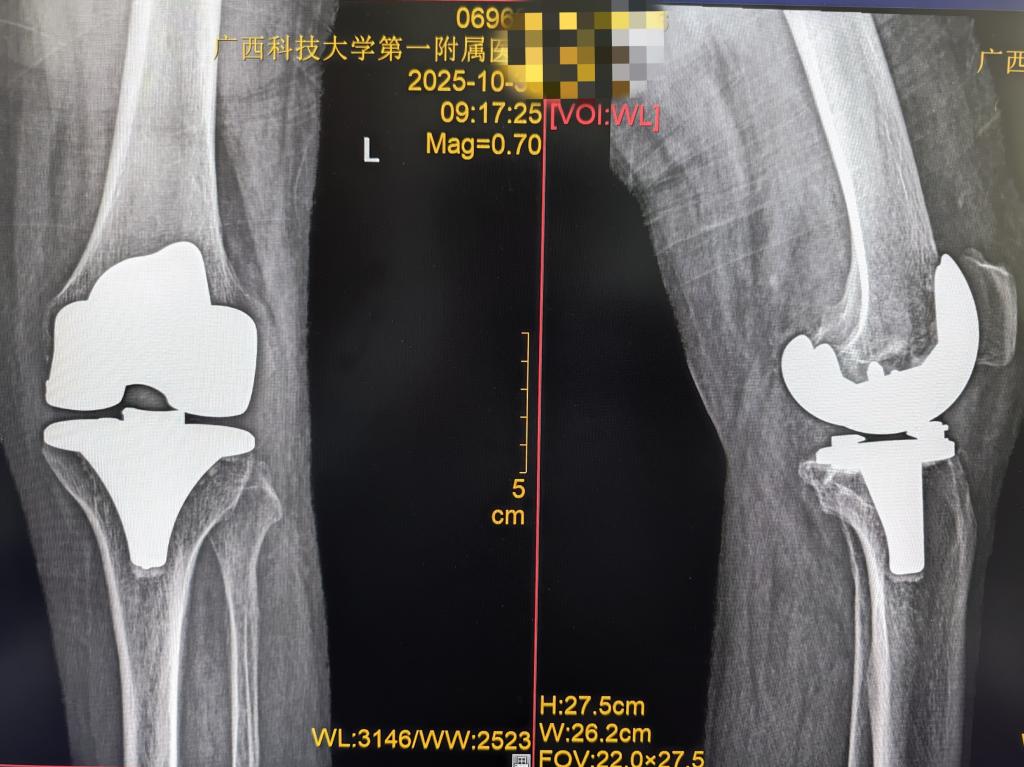

人工全膝关节置换术(TKA)是严重膝关节疾病的终末治疗手段,可改善膝关节功能,但需配合科学术后康复训练,否则易出现膝关节僵硬,无法达到手术应有的疗效,规律活动以恢复关节灵活性、肌肉力量及日常活动能力,是术后康复的关键。